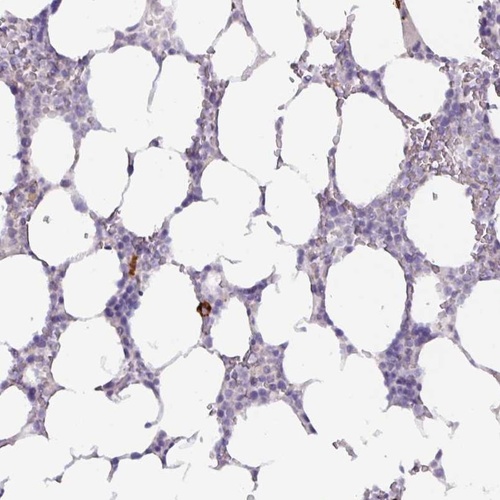

Immunohistochemical staining of human bone marrow shows cytoplasmic positivity in hematopoietic cells.